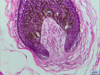

pacinian corpuscle